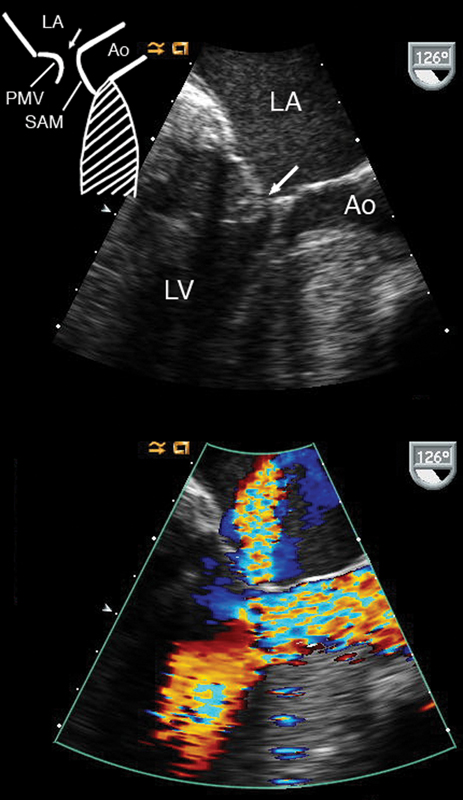

فحوصات تشخيصية لبعض امراض القلب والشرايين التاجية